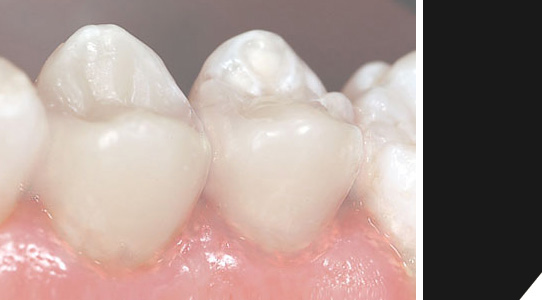

Wahl- o. Kassenleistung | Keramikfüllung

Die "Batterie im Mund". Amalgam ist ein äußerst umstrittenes Thema. Immer noch gehört eine Füllung mit diesem giftigen Material zur Kassenleistung. Aufgrund des unschönen Erscheinungsbildes und des allergieauslösenden Befundes bei manchen Patienten, entscheiden sich viele nach einigen Jahren sowieso dafür, Ihre Füllungen beispielsweise durch hochwertige Keramik ersetzen zu lassen.